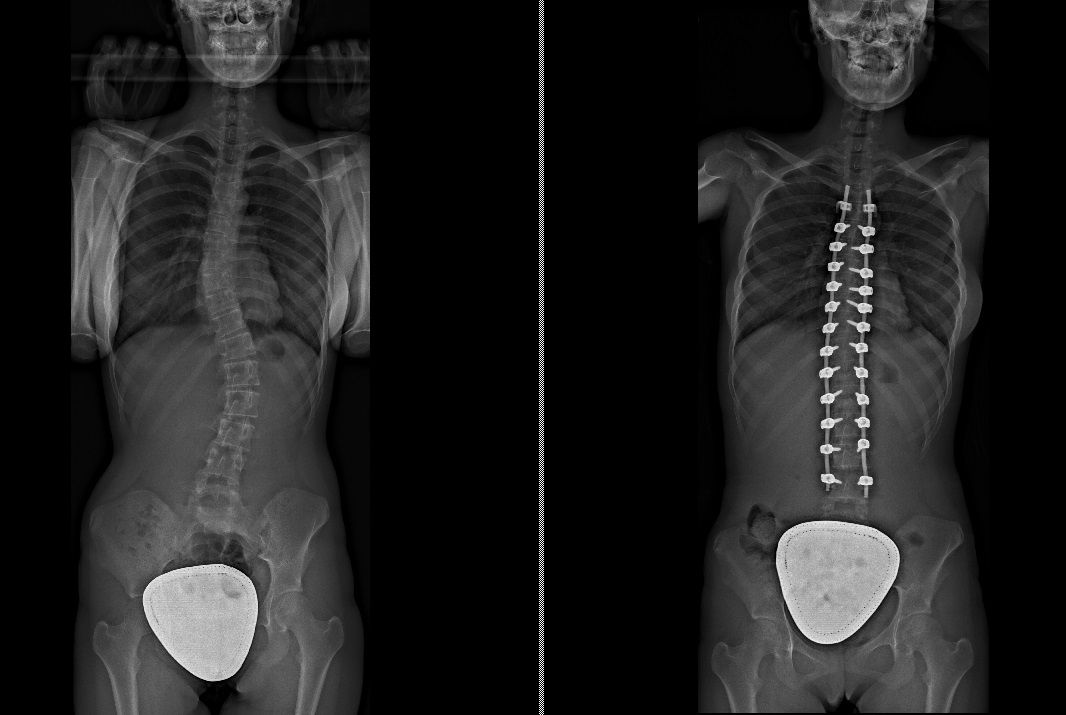

Laureato in Medicina e Chirurgia presso l'Università degli Studi di Napoli Federico II nel 2011, Specializzato in Ortopedia e Traumatologia presso la stessa Università nel 2017. Da subito ho dedicato i miei studi all'ambito della chirurgia vertebrale e della neurochirurgia. Infatti ho frequentato per 9 mesi tra il 2015 ed il 2016 i reparti di Neurochirurgia dell'IRCCS Neuromed di Pozzilli (IS) per apprendere le tecniche di trattamento delle Patologie della Colonna Vertebrale. Da allora il mio principale interesse è rivolto al trattamento conservativo e, dove necessario, chirurgico delle deformità della colonna vertebrale, sia dell’età dell’accrescimento che degenerative dell’adulto: scoliosi, dorso curvo, spondilolisi, spondilolistesi. Ulteriori campi di interesse sono il trattamento di lombalgia e lombosciatalgia, ernia del disco, stenosi del canale vertebrale, fratture vertebrali traumatiche o da osteoporosi (vertebroplastica), terapia del dolore osteoarticolare mediante tecniche mininvasive (radiofrequenze). Dal 2017 sono Consulente presso IRCCS Neuromed di Pozzilli (IS) con incarico di Responsabile del Centro per la Diagnosi e Cura delle Deformità Vertebrali e Scoliosi, dove svolgo la mia attività chirurgica in regime di convenzione. Svolgo la mia attività chirurgica in regime di solvenza e di convenzione assicurati presso la Clinica Ruesch di Napoli. Continuo costantemente la mia formazione con esperienze di perfezionamento nazionali ed internazionali. Infine, dal 2020 sono Docente per l'Università degli Studi di Roma "La Sapienza".

Foto e video